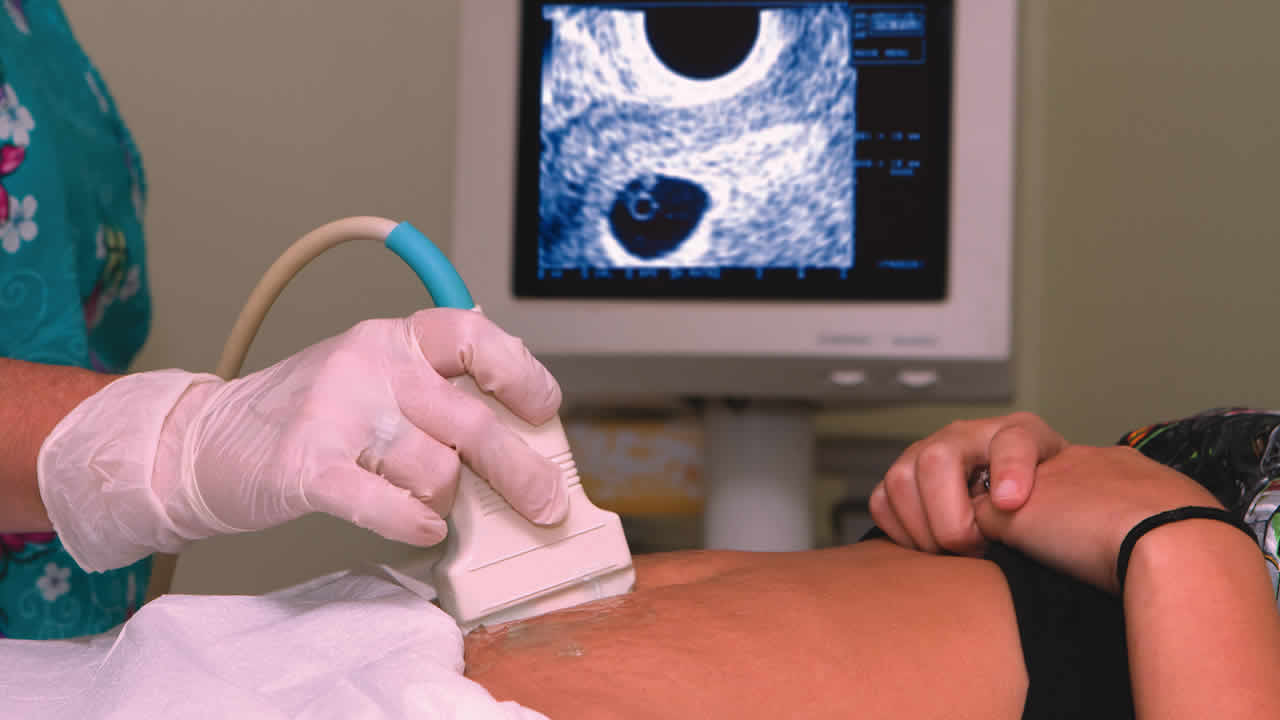

Elle a tenté de mettre fin à sa grossesse. Une habitante de D’Épinay, 28 ans, enceinte de six semaines, a avalé dix comprimés pour pouvoir avorter. Souffrant d’une hémorragie, elle a été admise à l’hôpital SSRN, à Pamplemousses. Sangeeta (prénom modifié), mère de deux enfants âgés de trois et neuf ans, saignait aux parties intimes depuis plus de cinq jours. Le jeudi 5 mai, elle a été conduite à l’hôpital par ses proches où elle a été admise. Le lendemain, elle a subi une échographie. Le personnel soignant a alors constaté qu’elle est enceinte de six semaines. Le médecin lui a demandé de suivre des traitements vu qu’elle est enceinte, mais Sangeeta a catégoriquement refusé de se faire soigner. Interrogée sur la cause de son refus, elle a expliqué qu’elle avait avalé dix comprimés abortifs pour mettre fin à sa grossesse. Son cas a été référé au poste de police de l’hôpital. L’époux de la jeune femme, âgé de 37 ans, a été interrogé dans le cadre de l’enquête. Il a nié le fait que sa femme ait pris des comprimés pour mettre fin à sa grossesse. « Mo madam pas kone mem ki ete konprime zot pe mansione. Je l’ai rencontré à l’hôpital et elle m’a dit que le médecin a voulu lui donner une injection. Mais elle a refusé car elle a peur de la piqûre. Ainsi, selon les dires de ma femme, le personnel soignant lui aurait demandé si elle avait pris des comprimés d’un certain nom. Dans un moment de panique, mon épouse a dit qu’elle les a pris. Elle a bel et bien pris des comprimés car elle se sentait mal. Ce ne sont pas des pilules abortives mais du Panadol », a expliqué le père de famille au Défi Quotidien. Ce mécanicien explique que sa femme est traumatisée. Sangeeta devra donner sa version complète à la police dès qu’elle se rétablira. Le dossier sera transféré au poste de police de Montagne-Longue pour les besoins de l’enquête.